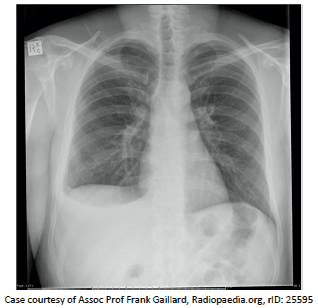

Um paciente de 45 anos é atendido em um ambulatório. Ele apresenta: queda do estado geral e sensação de febre. Ele traz uma radiografia de tórax em posição póstero-anterior realizada recentemente.

Esta radiografia revela